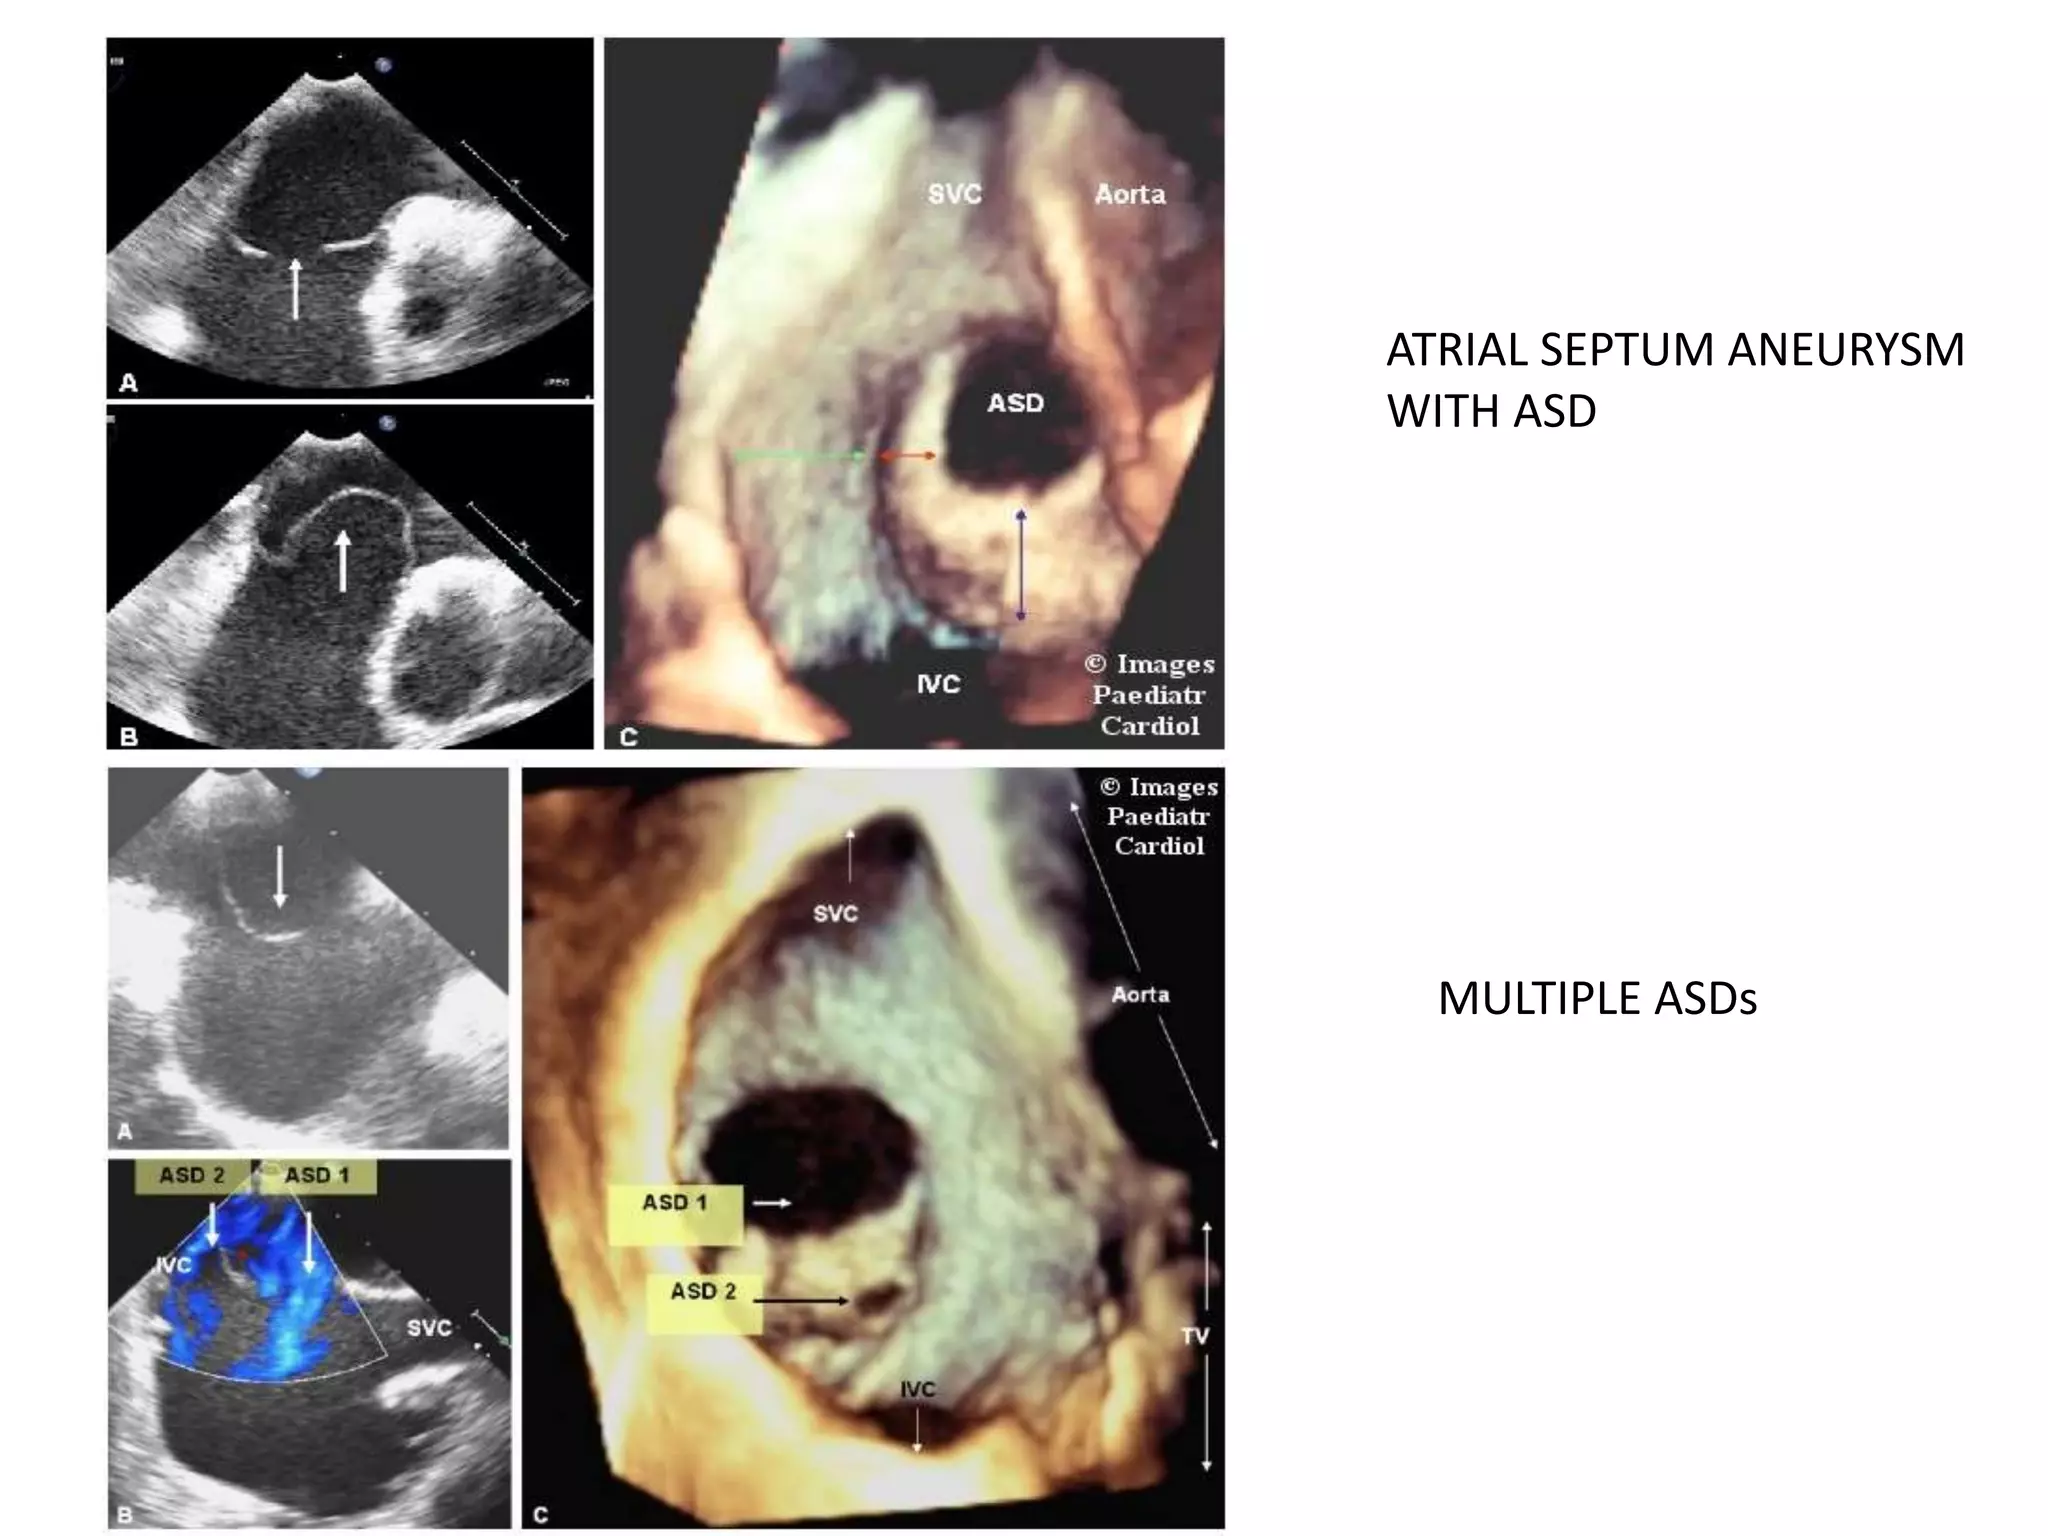

ATRIAL SEPTAL ANEURYSM

CRITERIA

A-PROTRUSION OF ANEURYSM ATLEAST

15MM OF PLANE OF IAS OR IAS SHOWING

15MM OF PHASIC EXCURSION DURING

CARDIORESPIRATORY CYCLE

B- BASE WIDTH≥ 15MM

ATRIAL SEPTUM ANEURYSM

WITH ASD

MULTIPLE ASDs

ATRIAL SEPTAL ANEURYSM CRITERIA A-PROTRUSIONOF ANEURYSM ATLEAST 15MM OF PLANE OF IAS OR IAS SHOWING 15MM OF PHASIC EXCURSION DURING CARDIORESPIRATORY CYCLE B- BASE WIDTH≥ 15MM

ATRIAL SEPTUM ANEURYSM WITHASD MULTIPLE ASDs